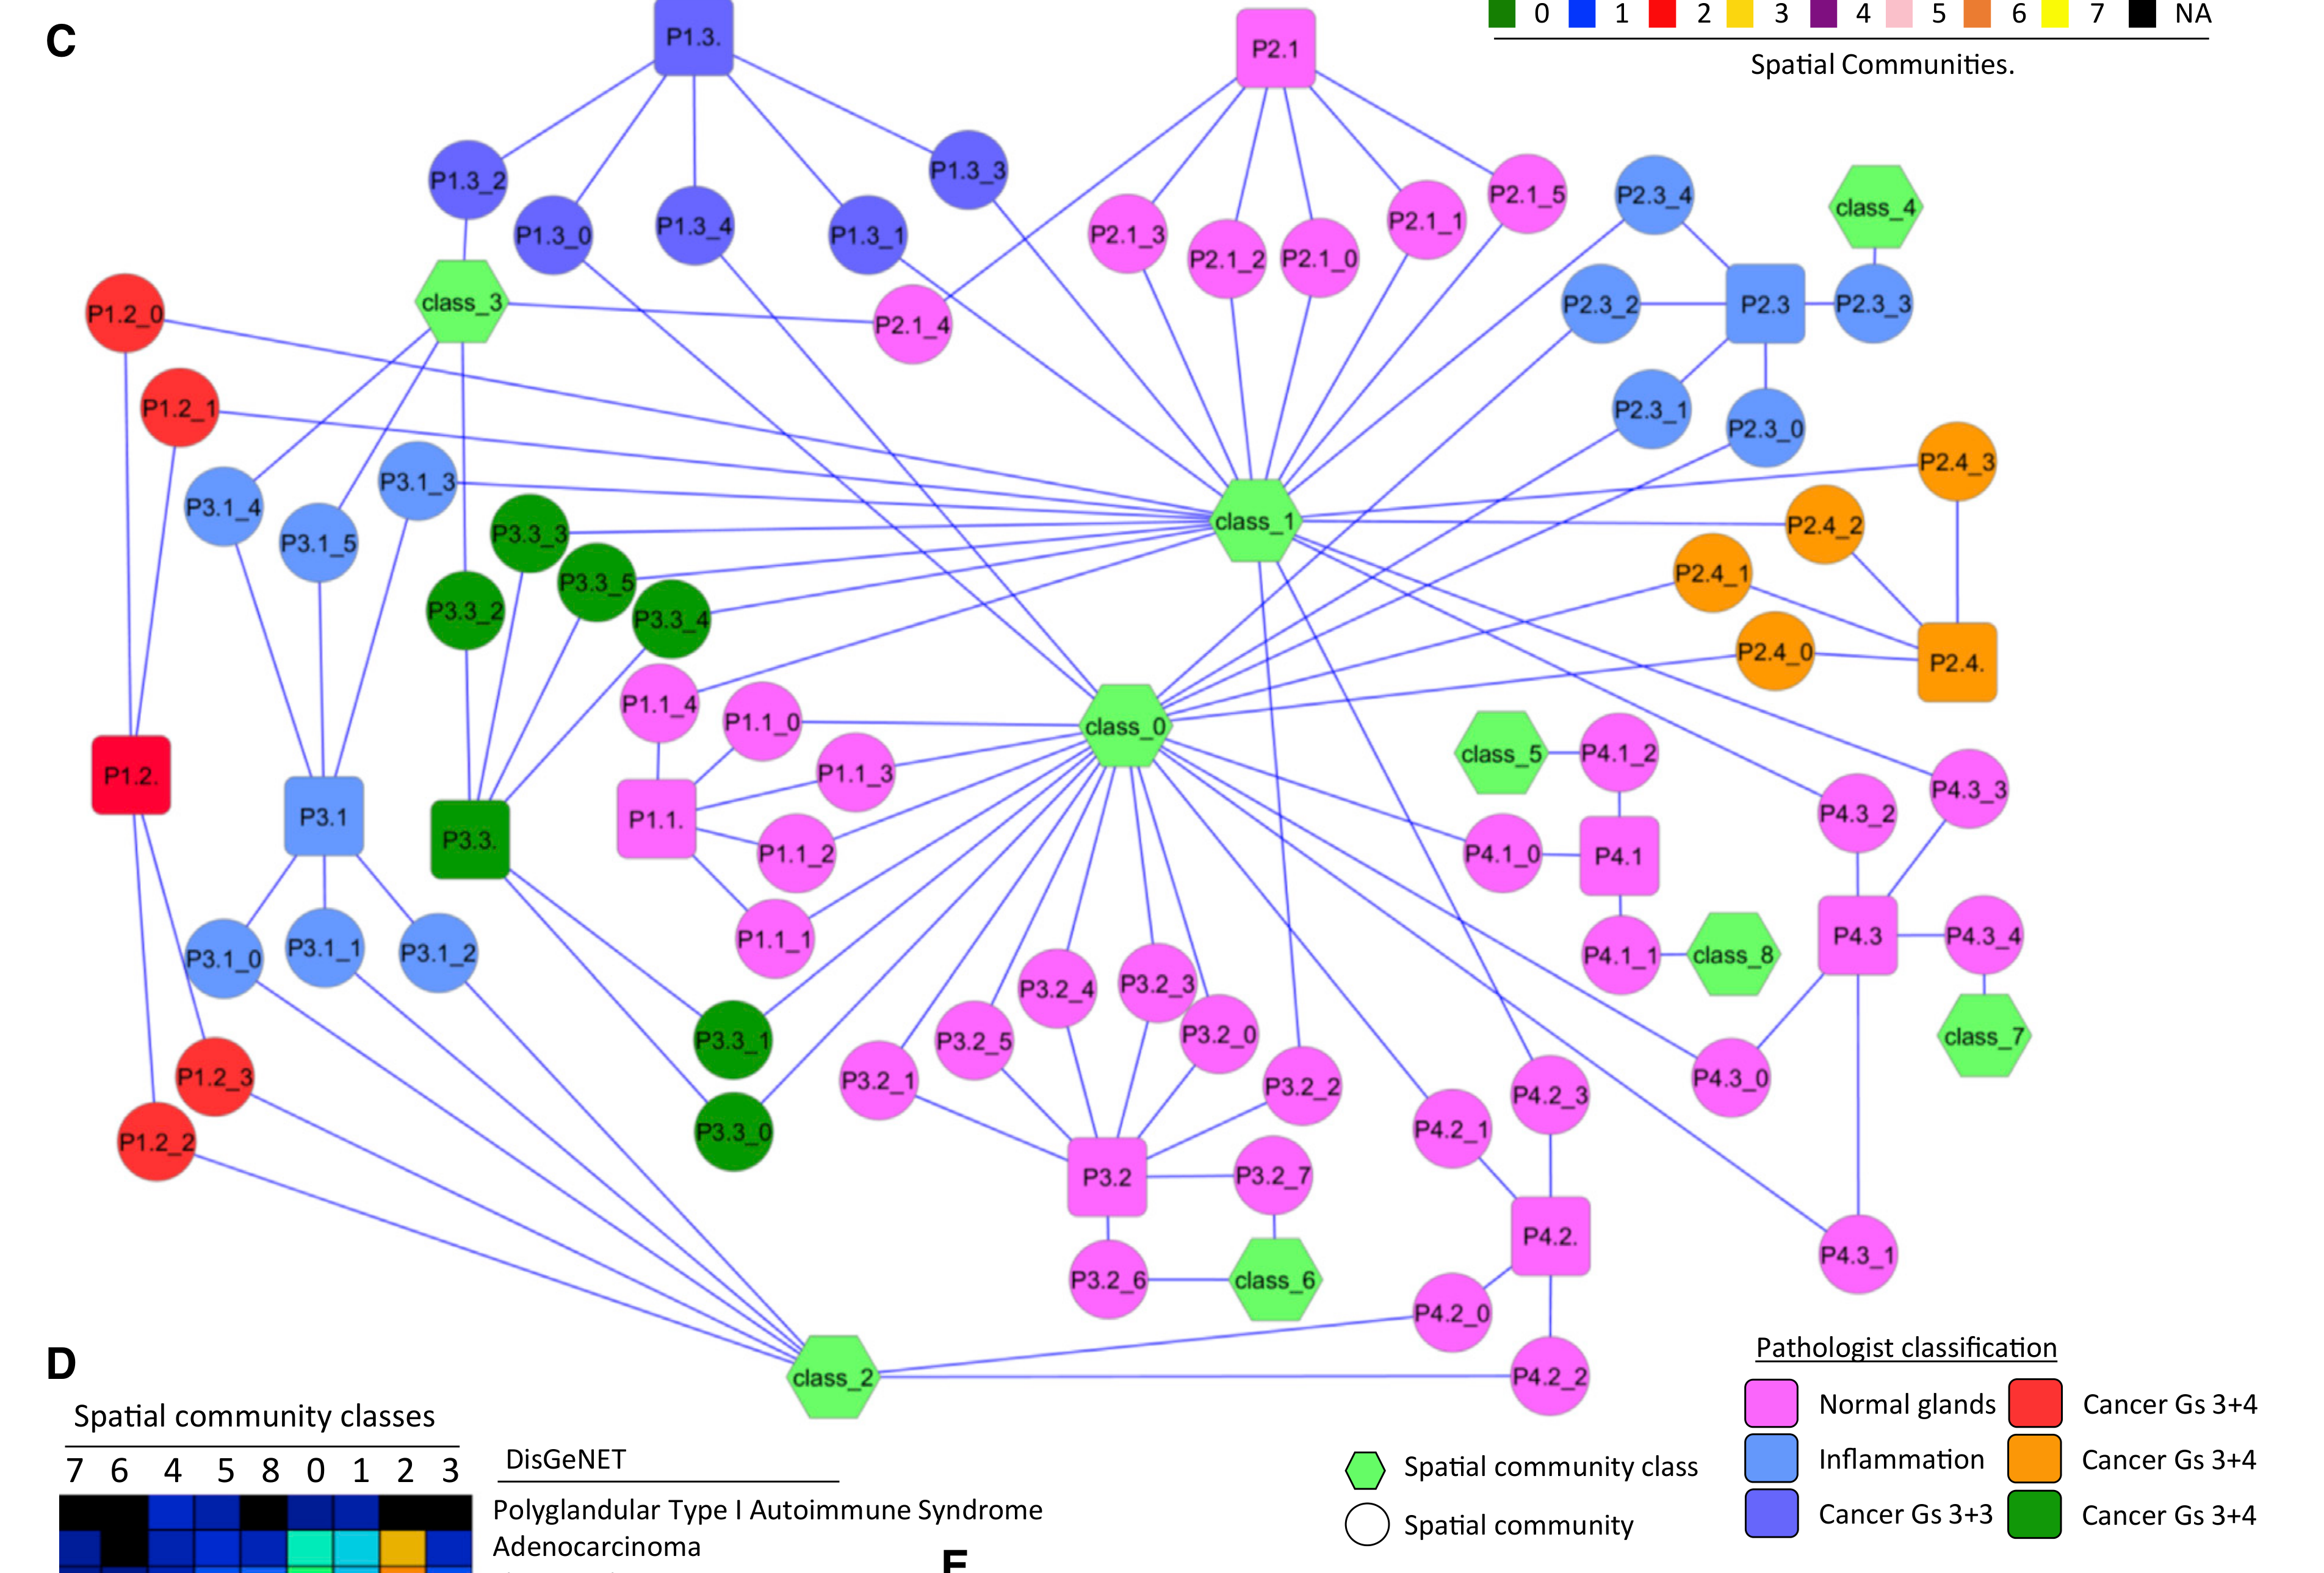

Benjamin K. et al. - 2024

Multiscale topology classifies cells in subcellular spatial transcriptomics

Condition Dimension

Categorical

Data Components

Biological AnnotationGene Expression Matrix

Data

Modality

Imaging-based

Resolution of observation

Sub-cellular

Visualized Elements

ObservationStatistic

Biological

Cellular

Abstraction

Partial

Chart Type

Pixel Map

Communicative/Contextualization

Annotation

Comparative Design

Juxtaposition : Small multiples

Layout

Spatial : Physical

Scalability Strategy

None (Item-level)

Where are specific cell types spatially located across treatment conditions?